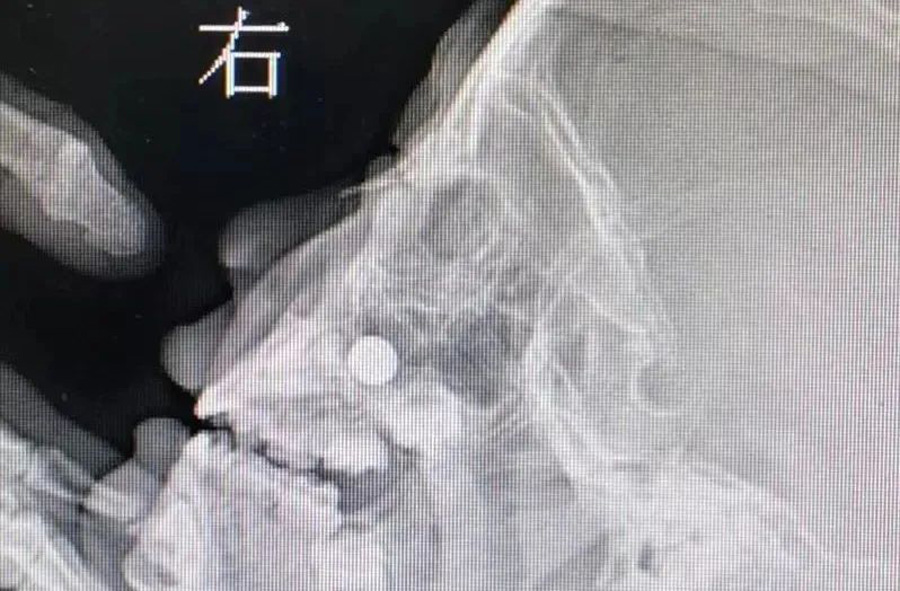

3月23日,120急救车将1名患儿送至德州扑克游戏网 。患儿3岁,来时明显看出鼻子不舒服。妈妈说,前一天儿子把纽扣电池塞右侧鼻子里了,但在当地医院没取出来。如果真的是纽扣电池,那就危险了,因为电池产生的腐蚀性物质及微电流会造成鼻腔黏膜腐蚀伤,甚至后期可能出现鼻中隔穿孔。门诊医生接诊后,未能看到鼻道中有明显异物,耳鼻喉科开放急危重症绿色通道。由于患儿及家长核酸结果未回报,耳鼻喉科医生在三级防护下做了鼻咽镜检查。在患儿下鼻道底部,发现有黏膜肿胀以及典型的纽扣电池异物放电导致的“冒泡”现象,但异物被肿胀的黏膜包裹,大小及形态显示不清。鼻咽部平片同样显示鼻腔底部有圆形金属异物。

由于异物位置特殊,以及患儿不配合,门诊不能顺利取出异物,急诊全麻取出是最好的办法。在全麻下,耳鼻喉科副主任李莉萍经过20多分钟定位、钩取,才将异物取出来。取出的纽扣电池颜色发黑,患儿右侧鼻腔黏膜也已被腐蚀成了黑褐色。经过给药处置、鼻腔消炎等治疗,第三天患儿出院回家了,后期需定期复查。